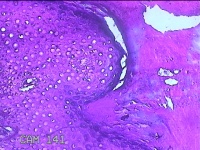

左足部包块

性别

女

年龄

34岁

临床诊断

皮下囊肿

一般病史

发现左足部包块4年余,无明显疼痛及不适。

标本名称

大体所见

灰白暗红色组织1.8x1.1x0.8cm一块,表面带梭形皮肤1.8x0.8cm,皮下见包块1。8x0.8x0.7cm一个,切开包块呈实性,切面灰白粉红色,质软。

图4